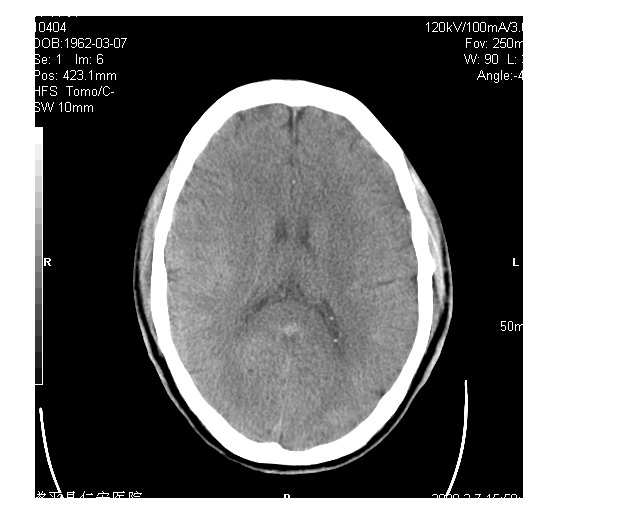

男36岁,外伤进行ct检查时发现脑实质及脑室旁多个细结节状影。是囊虫病吗?

脑内及脑室内可见多发性结节影,脑囊虫病不能除外,建议强化扫描或mri。

有吗?我只看见图象噪声致颗粒粗大,未见异常。建议加大mas

只看到左侧脑室内多发钙化.可以做结合补体实验啊.但未必阳性.还是隔期复查.mr 也未必定啊.